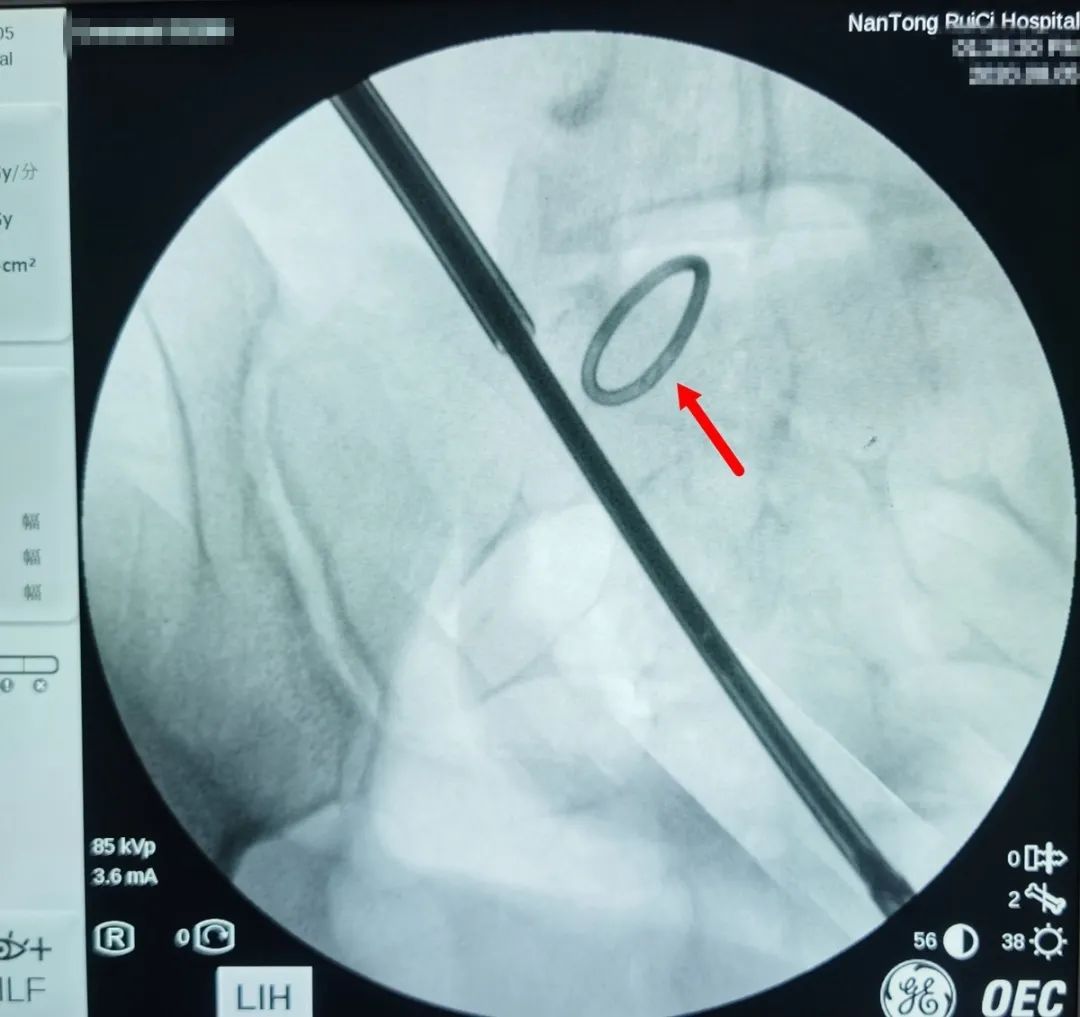

△術(shù)中X光,可清晰看到節(jié)育環(huán)。

△通過術(shù)中X光,對(duì)節(jié)育環(huán)進(jìn)行標(biāo)記定位。

通過反復(fù)的X光定位,醫(yī)生終于發(fā)現(xiàn)了節(jié)育環(huán)的蹤跡,這枚“O”型節(jié)育環(huán)已經(jīng)跑到了乙狀結(jié)腸中段右側(cè)系膜內(nèi),并且穿透了乙狀結(jié)腸右側(cè)壁肌層,貫穿腸腔。醫(yī)生分離切開腸系膜后,看見有近一半的節(jié)育環(huán)嵌頓在腸腔內(nèi)。